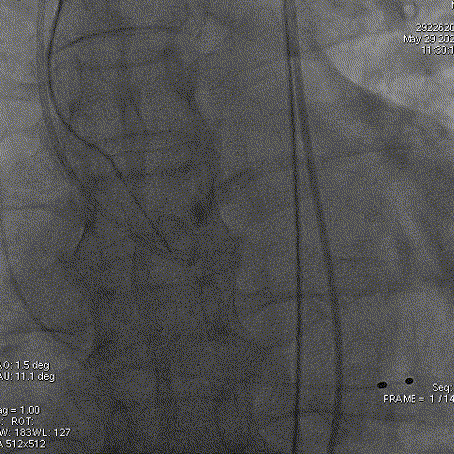

术后即刻超声评估:

术后压差从42mmHg降至15mmHg,前向血流从4.7m/s降至2.7m/s

术后超声心动图提示:主动脉瓣人工瓣膜前向血流2.7m/s,平均垮瓣压差约15mmHg,少量瓣周漏,左室壁搏幅正常范围,心包未见积液,手术效果良好。